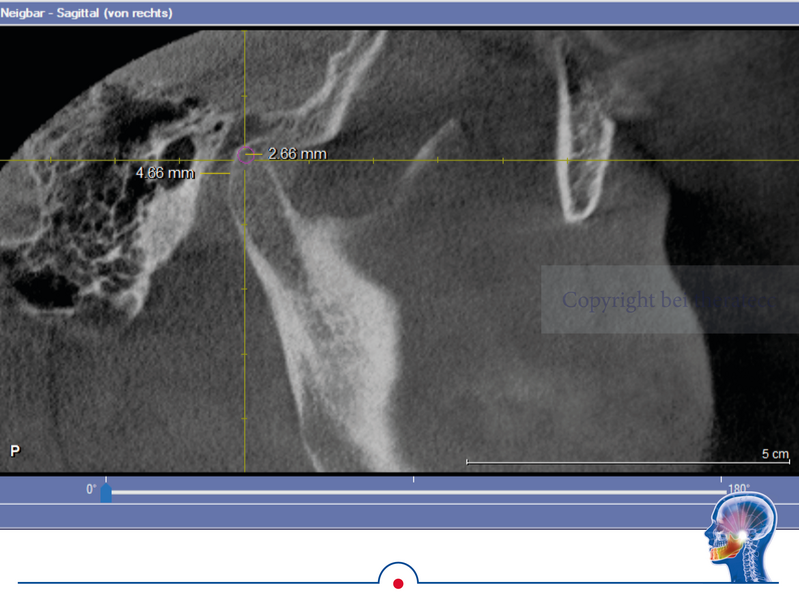

Grundsätzlich ist es logisch, dass die habituelle Okklusion den Patienten in

seine jeweilige Kondylenposition „zwingt“. Das kann man sehr schön bei einer

DVT-Aufnahme erkennen, wenn diese ohne frontalen Aufbiss in habitueller Okklusion realisiert wird.

In dem DVT wird sichtbar, dass der linke Kondylus in habitueller Bisslage um

ca. 2,5 mm deutlich zu anterior positioniert ist. Ursache dafür ist der Zahnkontakt bei 26 und 36. Dieser Zahnkontakt zwingt den Unterkiefer linksseitig in die anteriore Kondylenposition. Wenn jetzt in diesem Gebiss eine klassische Handbissnahme für eine Zahnversorgung durchgeführt wird, wird diese „falsche Kondylenposition“ in den Artikulator übertragen.